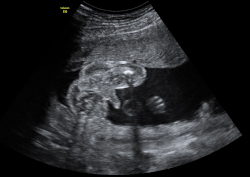

En la semana 20 de gestación, el aparato genital del feto ya es evidente, tanto en niñas como en niños con una ecografía en 4D. Los órganos genitales externos se formaron en la semana 12 de embarazo.

Cómo es el aparato genital femenino del feto en vídeo

En la imagen podemos apreciar un feto del sexo femenino con una edad gestacional de 20 semanas y 3 días.